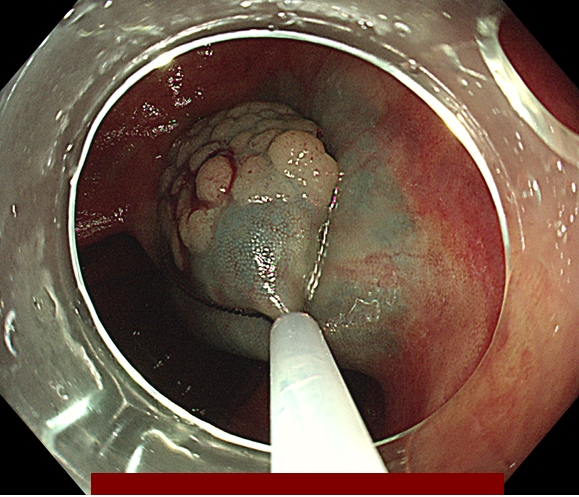

따라서 용종 절제를 하는 주된 이유 2가지는

① 모든 암성 조직을 완전하게 제거하기 위함이고

② 조직학적으로 평가될 수 있는 조직 샘플을 제공하기 위함입니다.

다음은 대장내시경 중 발견된 용종을 일괄 절제한 과정입니다.